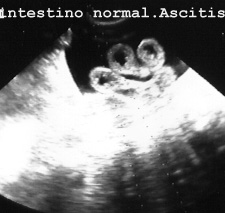

Las asas intestinales son muy visibles cuando hay ascitis o líquido dentro. En la (Fig 45A y 45B) se ve intestino delgado normal.